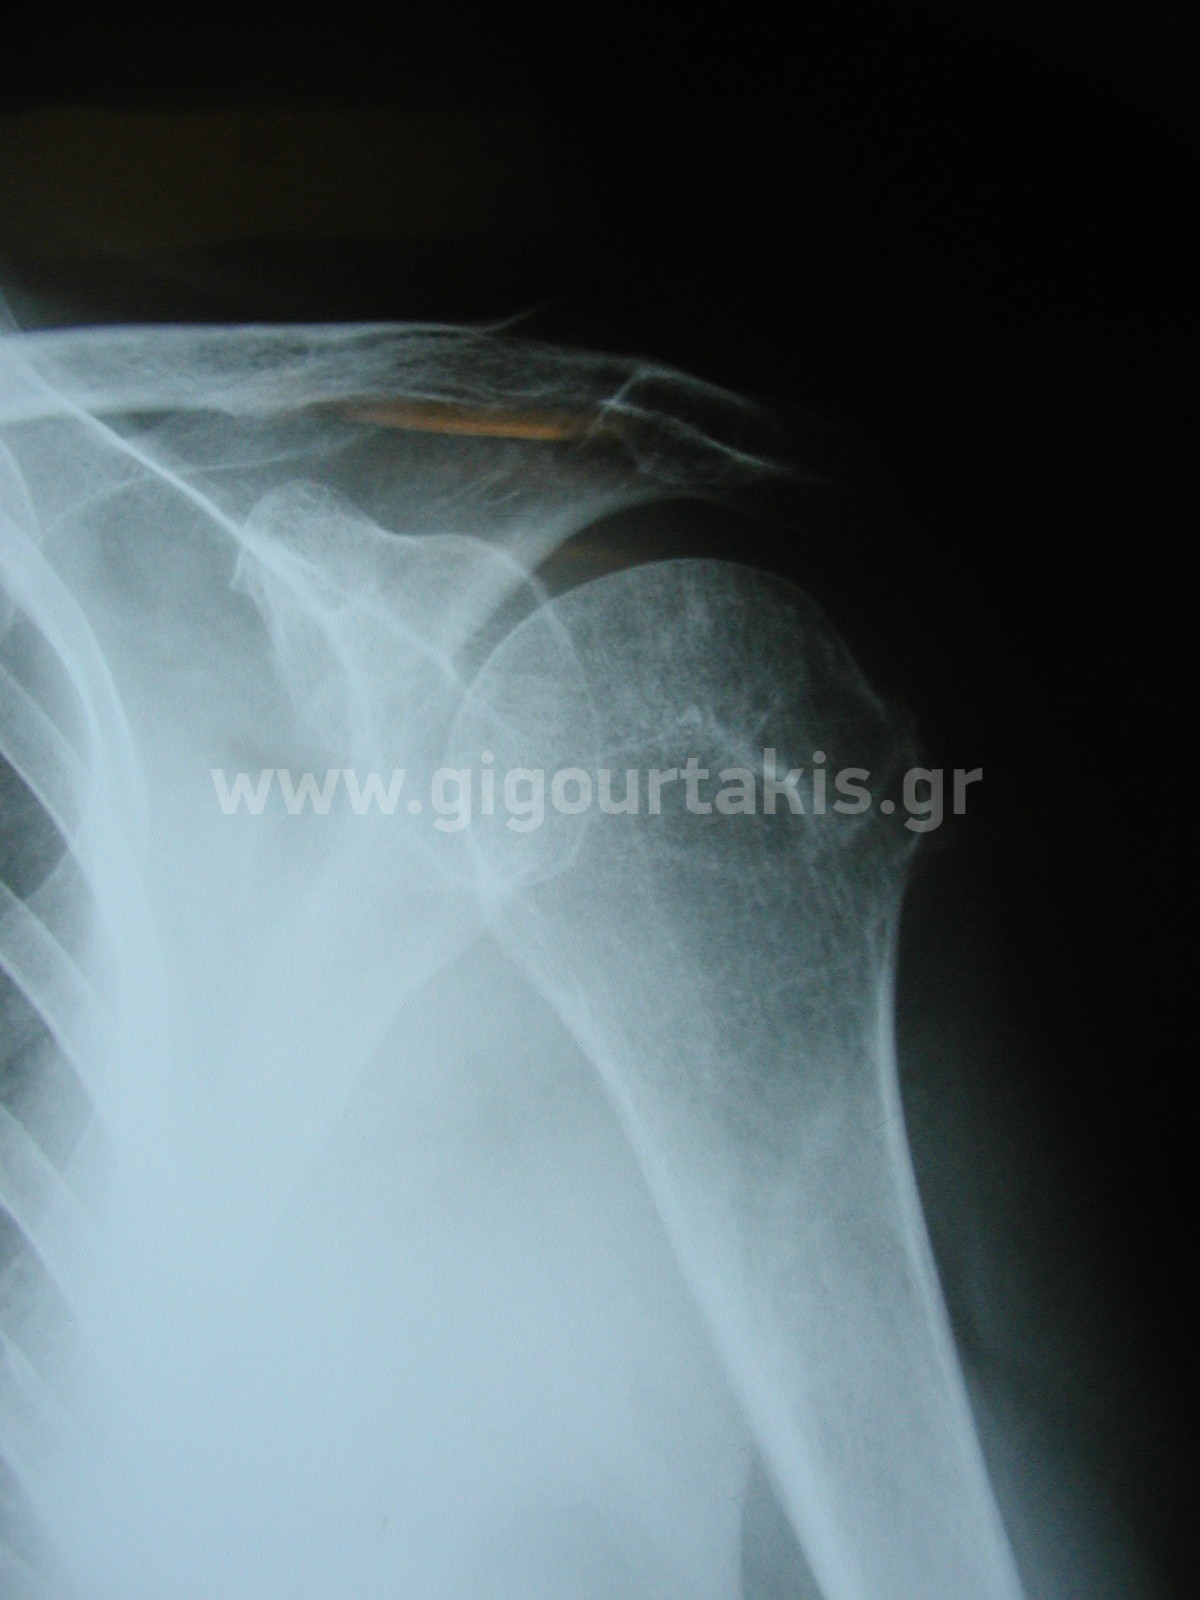

ΚΑΤΑΓΜΑ ΒΡΑΧΙΟΝΙΟΥ ΚΑΤΑΓΜΑ ΜΕΙΖΩΝΟΣ ΒΡΑΧΙΟΝΙΟΥ ΟΓΚΩΜΑΤΟΣ 01. 02.ΤΕΛΙΚΗ ΚΑΜΨΗ ΩΜΟΥ 03.ΤΕΛΙΚΗ ΑΠΑΓΩΓΗ ΩΜΟΥ2 04.ΤΕΛΙΚΗ ΕΞΩ ΣΤΡΟΦΗ ΩΜΟΥ 05.ΤΕΛΙΚΗ ΟΠΙΣΘΙΑ ΠΡΟΣΑΓΩΓΗ ΩΜΟΥ Στις κατηγορίες:ΑΝΩ ΑΚΡΟ, ΚΑΤΑΓΜΑ ΜΕΙΖΩΝΟΣ ΒΡΑΧΙΟΝΙΟΥ ΟΓΚΩΜΑΤΟΣ, ΩΜΙΚΗ ΖΩΝΗ ΒΡΑΧΙΟΝΙΟ, ΚΑΤΑΓΜΑTA